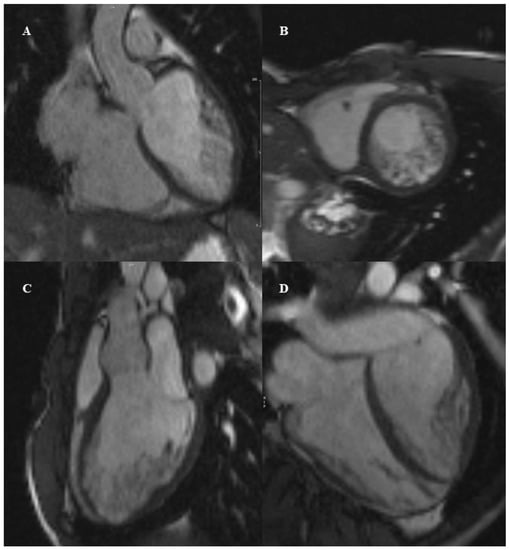

4. Hypertrophic Cardiomyopathy

CMR Diagnostic and Prognostic Role in Pediatric HCM